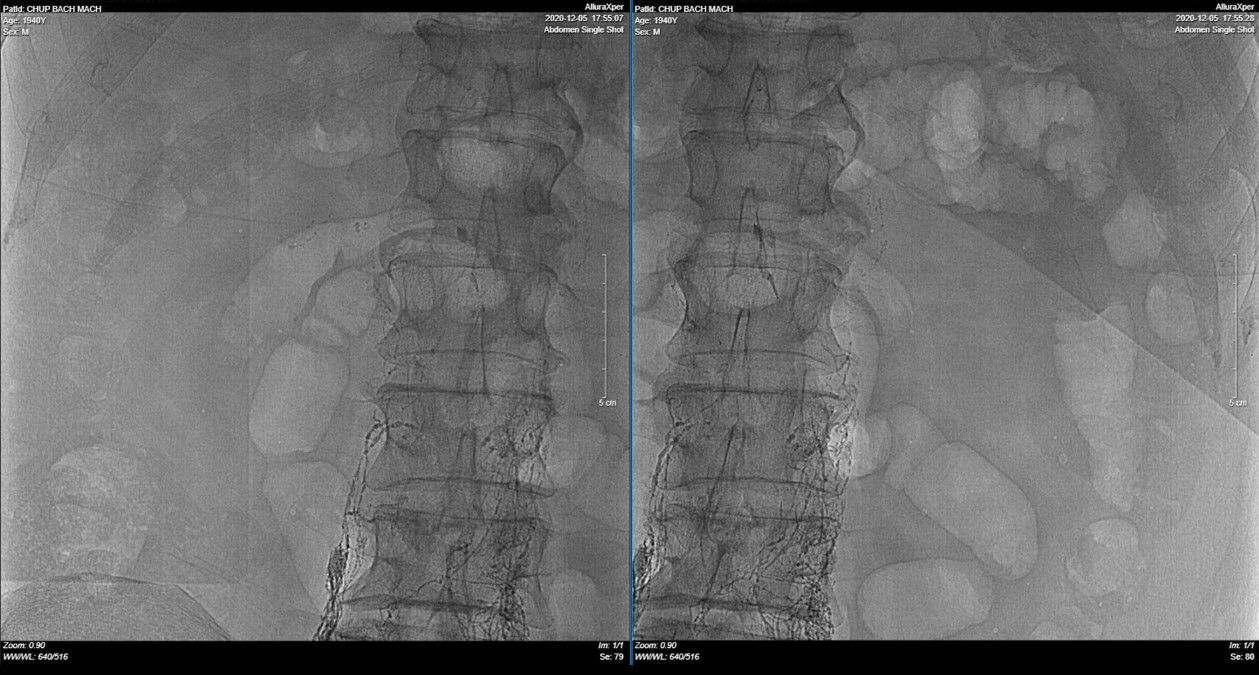

| Ảnh 1: Lipiodol được tiêm vào hạch bẹn hai bên, vào bạch mạch tiểu khung và di chuyển dần lên trên. | Ảnh 2: Lipiodol đi vào bạch mạch sau phúc mạc, sau đó đi vào bể dưỡng chấp, vào ống ngực, rồi đổ vào tĩnh mạch dưới đòn trái |